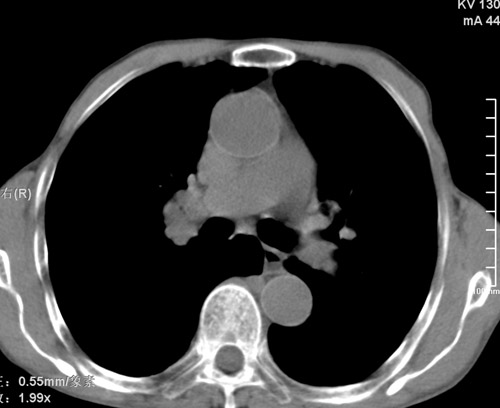

标题: CT17529:男 76 胸背部不适半月 胸透支气管炎 行CT检查 [打印本页]

标题: CT17529:男 76 胸背部不适半月 胸透支气管炎 行CT检查

意见 老年肺 少许炎症 肺大泡 右肺门略大 但支气管通畅  请各位高手指教如何下意见

支持楼主意见,右肺门略大,可能为肺动脉增粗.

慢支肺气肿,肺动脉高压.